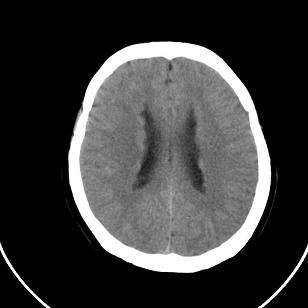

标题: CT20488:女,39岁,体检,双侧脑室有问题吗? [打印本页]

标题: CT20488:女,39岁,体检,双侧脑室有问题吗?

双侧脑室边缘呈波浪样,没有见过?

不知患者有无临床症状,双侧侧脑室边缘不规则,呈波浪状,考虑脑室周围白质软化症可能性大

影像学表现:软化灶分布于半卵圆中心和脑室周围白质,呈斑片状或长条状,多为双侧分布,脑室扩大,且脑室缘不规整。这是本症在影像学上的特点。

只有一层显示双侧侧脑室边缘不规则,呈波浪状,不排除部分容积效应,我做的话薄层再扫描一下

这个病例不符合脑室周围白质软化症

是不是应该考虑结节性硬化或者灰质移位,建议mri

1)脑灰质异位。2)双侧枕部颅骨内板下方类似扇形及弧形脑脊样低密度影;鉴别于巨大枕大池与蛛网膜囊肿之间。建议必要时行进一步检查。